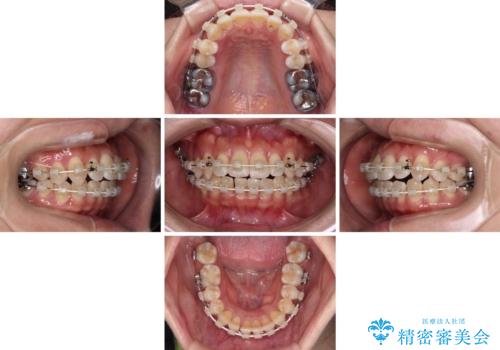

気になる八重歯 ワイヤー装置での非抜歯矯正

- 審美装置

- 2年6ヶ月

- 上顎の八重歯と全体的なデコボコを気にして来院された患者様です。

口元の突出感はなかったため非抜歯矯正での対応となりますが、八重歯を改善する際に上顎前歯が前突する可能性があったため、上顎臼歯部にアンカースクリューを使用して、歯列が前方に転位しないようにすることとしました。

また舌のトレーニングを行うことで、上顎前歯の突出予防や上下前歯に隙間ができなくなるようにしました。

ワイヤー矯正でもインビザラインでも対応可能でしたが、上顎歯列が前方位であるときには、ワイヤー矯正の方がより良い仕上がりとなる可能性が高いため、ワイヤー矯正をおすすめいたしました。